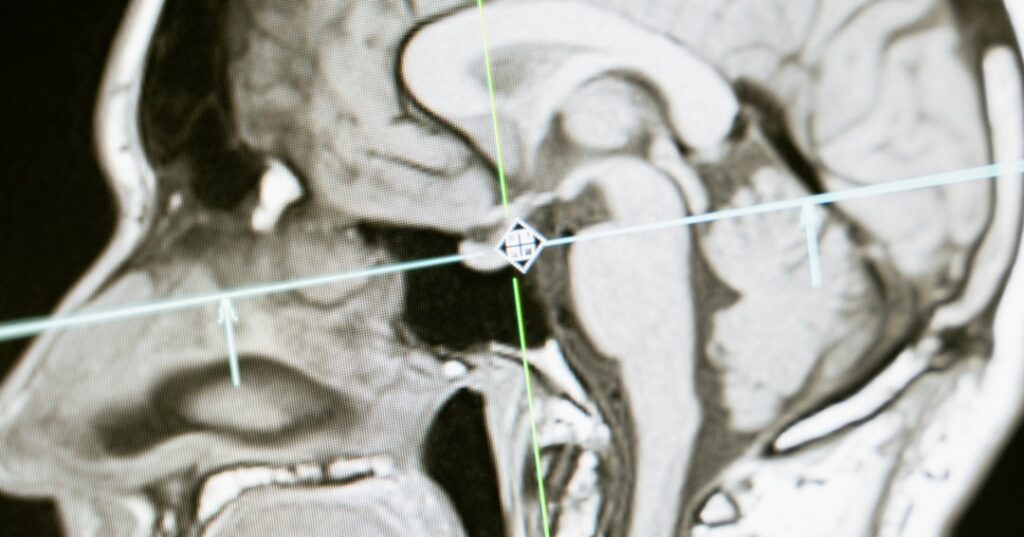

Científicos brasileños identificaron una sustancia con potencial para revertir los efectos del Alzheimer, especialmente los relacionados con el envejecimiento y la demencia. En pruebas con roedores de edad avanzada y deterioro cognitivo, el aumento de esta molécula mejoró las conexiones neuronales, mostrando resultados prometedores.

Con el paso del tiempo, las funciones cognitivas suelen deteriorarse: la capacidad de pensar, recordar, tomar decisiones o retener información se ve afectada. Este deterioro se agrava significativamente en presencia del Alzheimer. No obstante, este hallazgo abre la posibilidad de rejuvenecer el cerebro, acercándonos a tratamientos más eficaces para esta enfermedad.

La sustancia identificada por los científicos se llama hevina. Recientemente, reunieron evidencia que muestra cómo sus niveles son más bajos en pacientes con Alzheimer en comparación con quienes no padecen esta enfermedad.